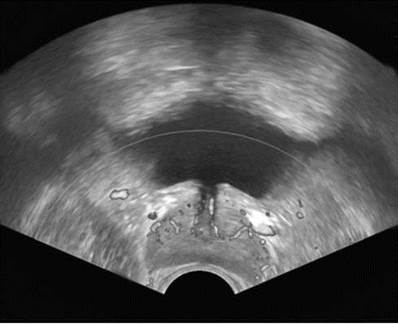

УЗИ мочевого пузыря возможно только при его адекватном наполнении мочой, когда складчатость слизистого слоя уменьшается. Визуализация мочевого пузыря возможна трансабдоминальным (рис. 4.15), трансректальным (рис. 4.16) и трансвагинальным доступом.

Рис. 4.15. Трансабдоминальная сонограмма мочевого пузыря в норме

Рис. 4.16. Трансректальная сонограмма мочевого пузыря в норме